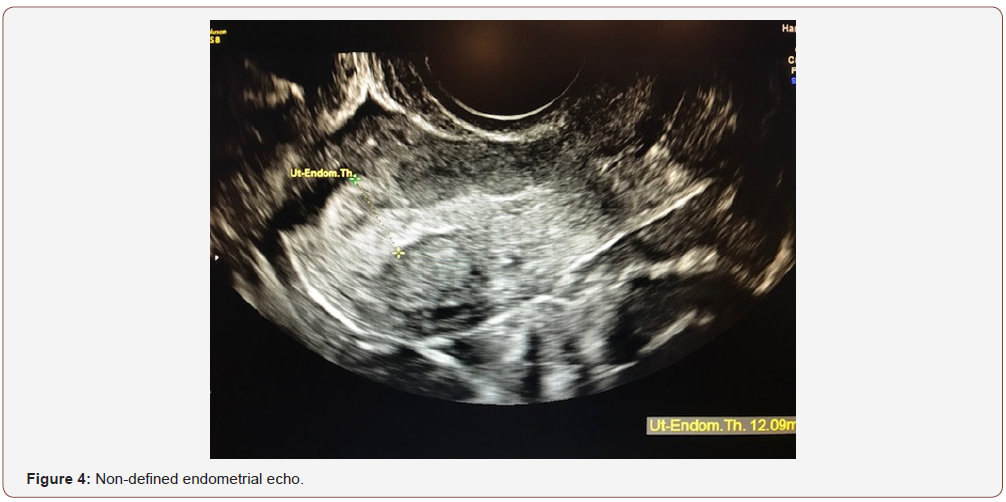

An evaluation of endometrial morphology included an assessment of endometrial echogenicity, the endometrial midline and the endometrial-myometrial junction. A ‘uniform’ endometrium included the three-layer pattern (Figure 1), as well as a homogenous hyperechogenic, hypoechogenic and is echogenic endometrium. The echogenicity is defined as ‘non-uniform’ if the endometrium appears heterogenous, asymmetrical or cystic (Figure 2). The endometrial midline was defined as ‘linear’ (Figure 3), if a straight hyperechogenic interface within the endometrium is visualized, as ‘non-linear’ if a waved hyperechogenic interface is seen, and as ‘irregular’ or as ‘not defined’ in the absence of a distinct interface (Figure 4). All studies were performed at the AIUM certified sonographic unit.